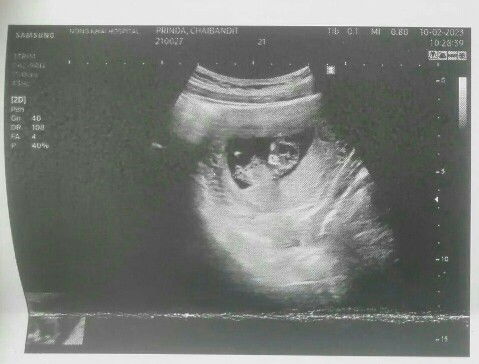

สวัสดีค่ะแม่ๆ ใครเคยมีประสบการณ์แบบนี้บ้างคะ ช่วงไปตรวจครรภ์ช่วงแรกๆเลยคือนับจากประจำเดือนค่ะ พออัลตร้าซาวด์ดู ห่างจากประจำเดือน 2 สัปดาห์ หมอเลยให้กำหนดคลอดตามผลอัลตร้สซาวด์ พอเริ่มๆ 20 w++ รู้สึกว่าน้องโตกว่าเกณฑ์ ไป 2 w เหมือนน้องโตเท่าประจำเดือนเลยค่ะ ตอนนี้ ถ้านับจากประจำเดือนก็ 36w แล้วค่ะ ขอบคุณสำหรับคำแนะนำนะคเ #ท้องแรก #ขอความคิดเห็นของคุณแม่หน่อยค่ะ